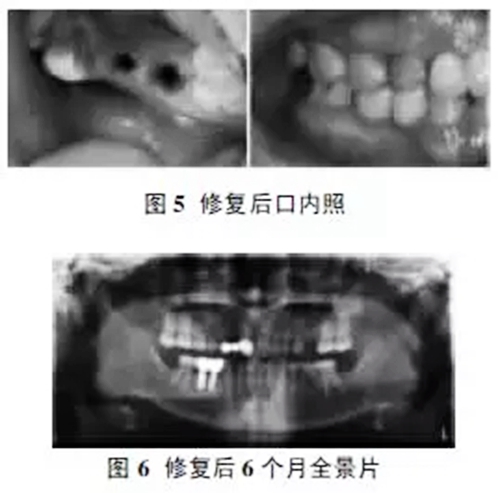

術(shù)后患者預(yù)后良好,種植體無松動(dòng),修復(fù)后患者主觀滿意度較好(如圖5)。修復(fù)6個(gè)月后全景片檢查種植體周圍無明顯骨吸收(如圖6)。